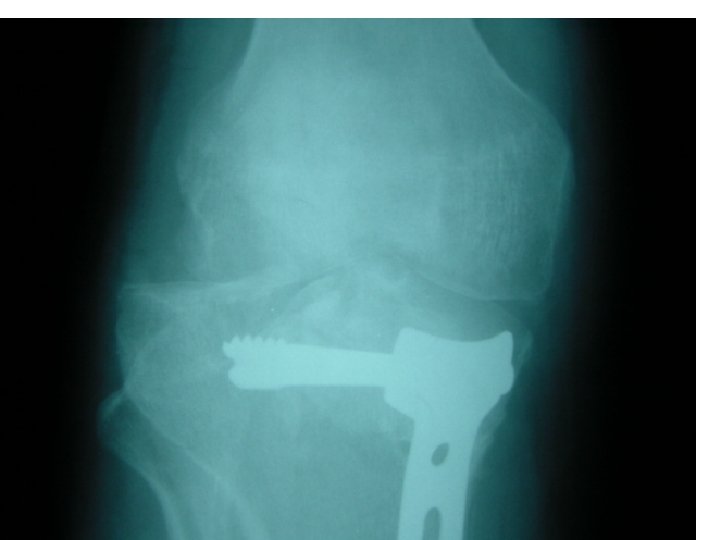

Open reduction 1 -displaced intra articular indications 2 -unstable Fr 3 -avulsion Fr 4

Open reduction 1 -displaced intra articular indications 2 -unstable Fr 3 -avulsion Fr 4 -Displaced pathologic Fr 5 - only operation indication 6 -Salter 3, 4 7 -compartment syn. 8 -NONUNION

Difinitive 1 -DEBRIDMENT 2 -FRACTURE TREATMENT A-INTERNAL FIXATION B-EXTERNAL FIXATION 3 - SKIN